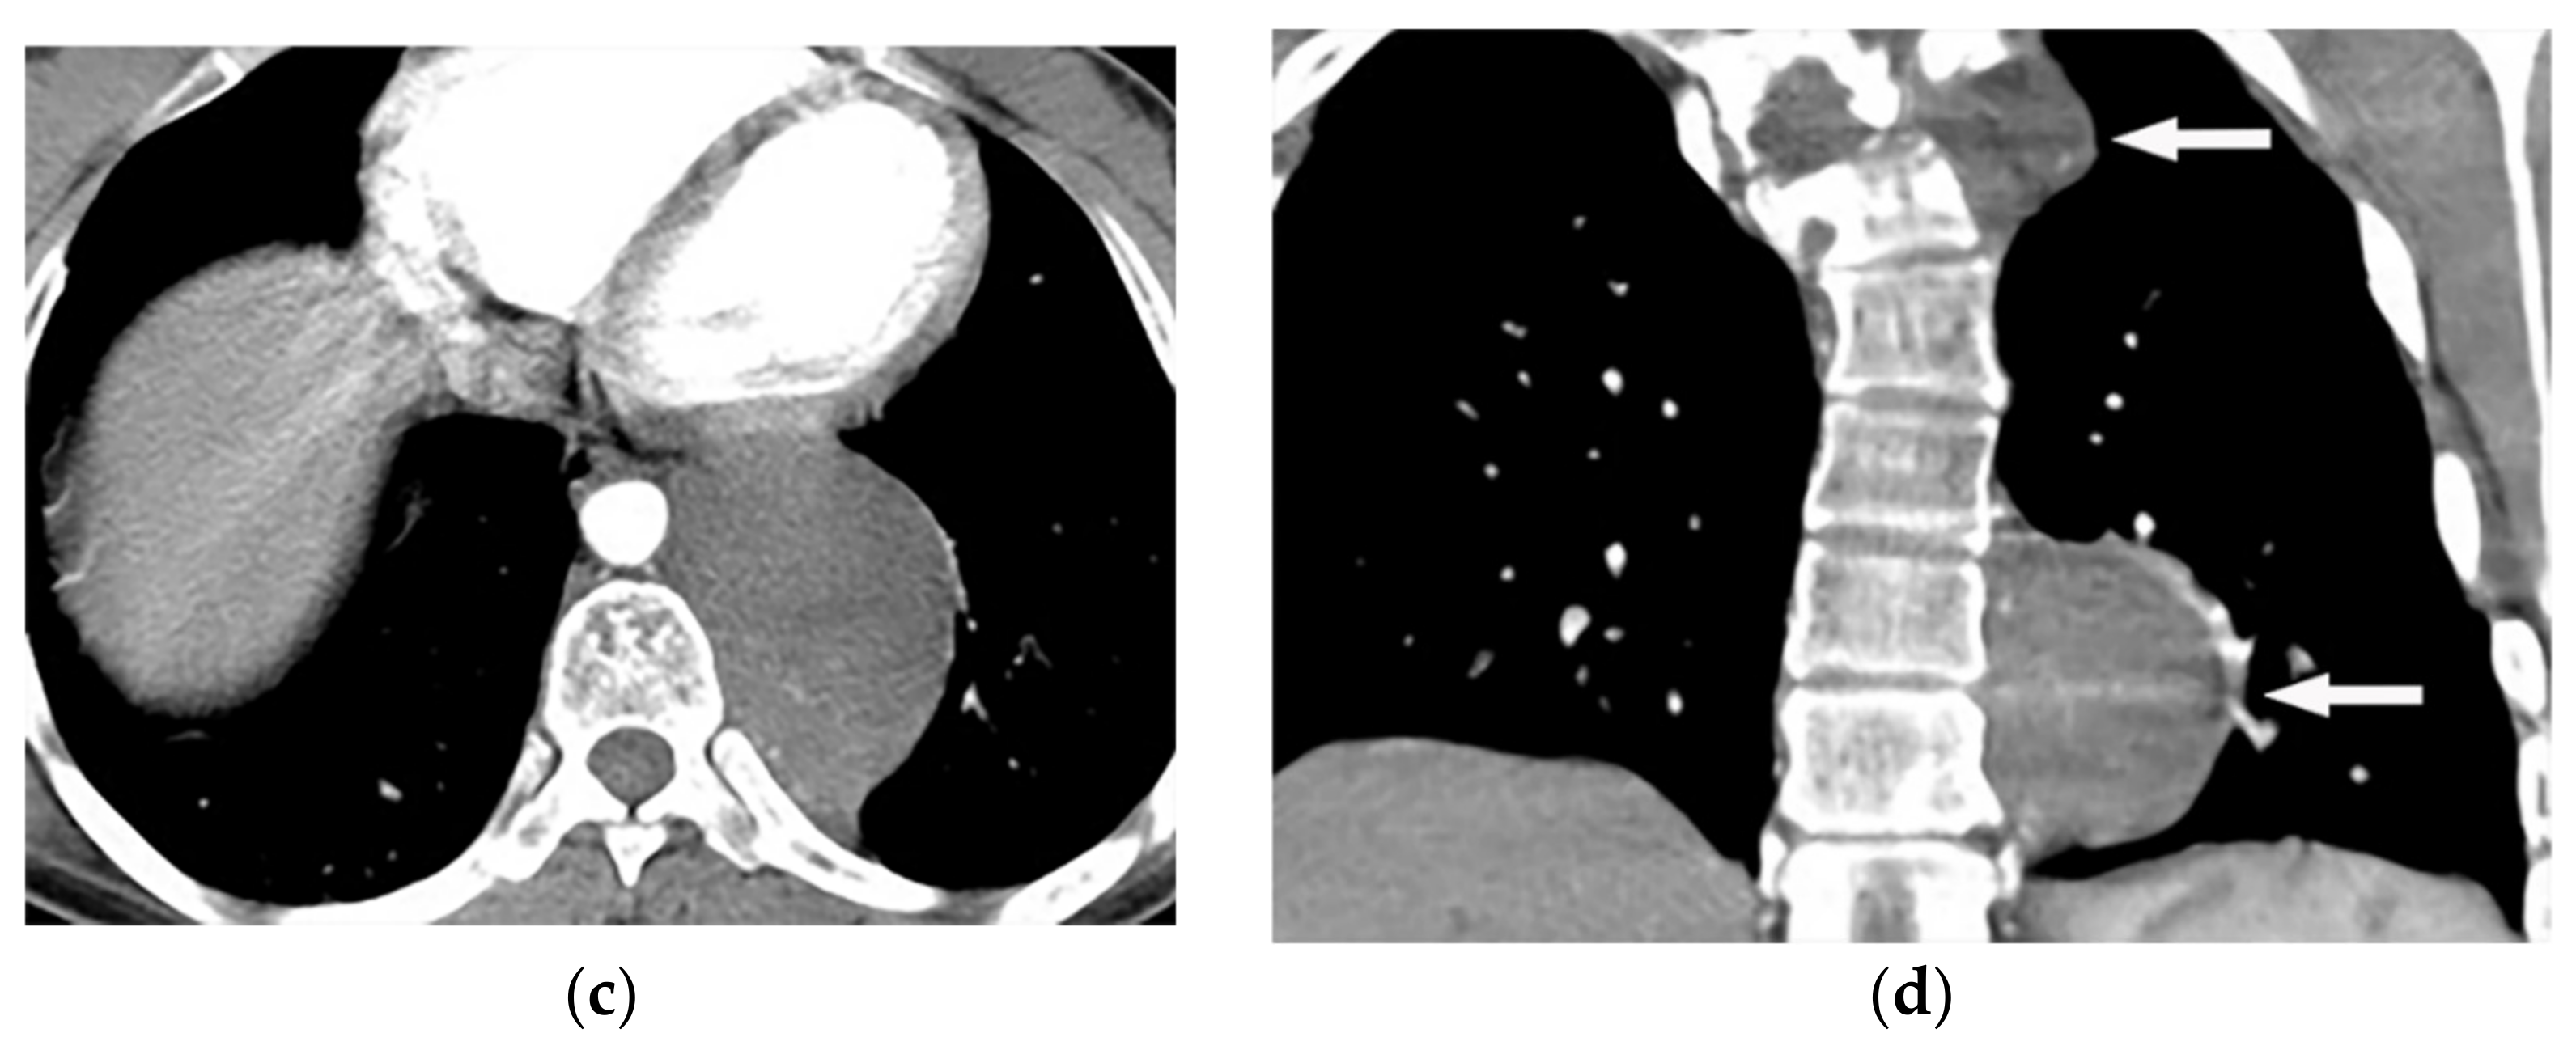

| Mesothelioma | Circumferential pleural thickening, bony or cartilaginous differentiation, unilateral pleural effusion, interlobular septal thickening, tumoral extension, thoracic and extrathoracic metastasis. | T1W: unilateral hyperintense pleural effusion, iso to slightly hyperintense pleural thickening T2W: moderately hyperintense T1WFS + C: typical enhancement is expected |